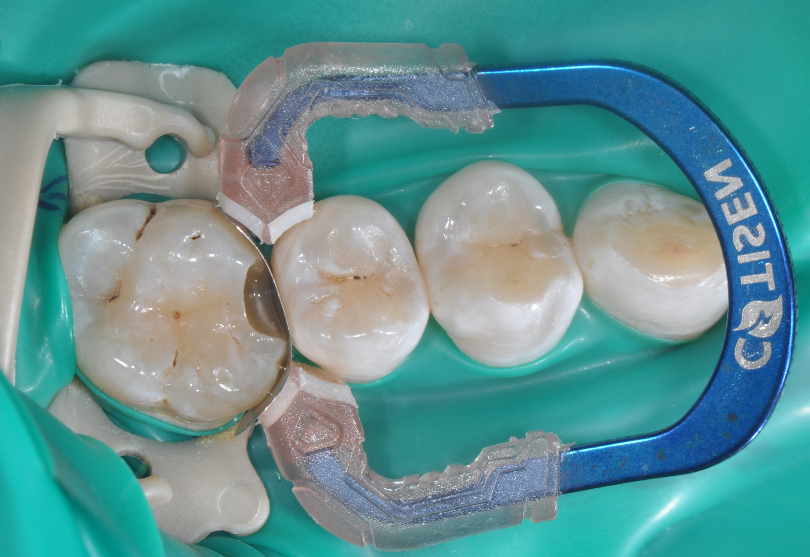

牙医-马小寒【实操病例】

右上6号牙位的近中,可见隐约龋坏